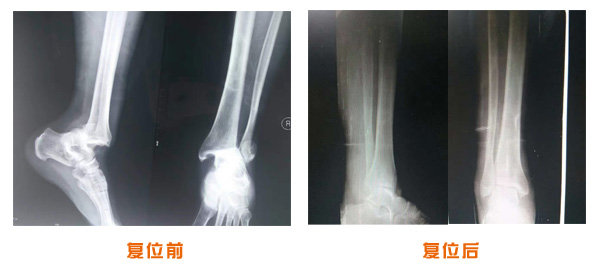

肥城市安駕莊梁氏骨科醫(yī)院是一所以梁氏手法正骨配合膏藥為特色的現代化??漆t(yī)院。

梁氏骨科術始創(chuàng)于清雍正年間,歷經八代,至今已有三百年歷史。據1929年泰安縣志載“梁瑞圖先生,字增生,號蓮峰,安駕莊人,精岐黃并發(fā)明接骨,凡跌打車凡跌打車軋皮不破而碎骨者......【詳細】 |